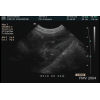

Foie

Durée. 2:46                 Dr Guy Beauregard